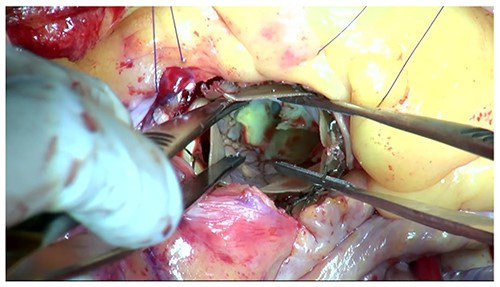

Moreover, the NCC calcification was shifted and protruded into the left ventricular outflow tract (LVOT), leading to an obstruction, as observed in the OR during the redo surgical AVR conducted due to the high transprosthetic gradient and PVL (Fig. 4). Subsequently, THV was extracted piece by piece, starting from the bare metal portion at the top followed by the frame and leaflet (Fig. 5). Then, decalcification was performed particularly around the NCC annulus and a bioprosthesis was implanted.

The protruding calcification into LVOT was identified in the OR.